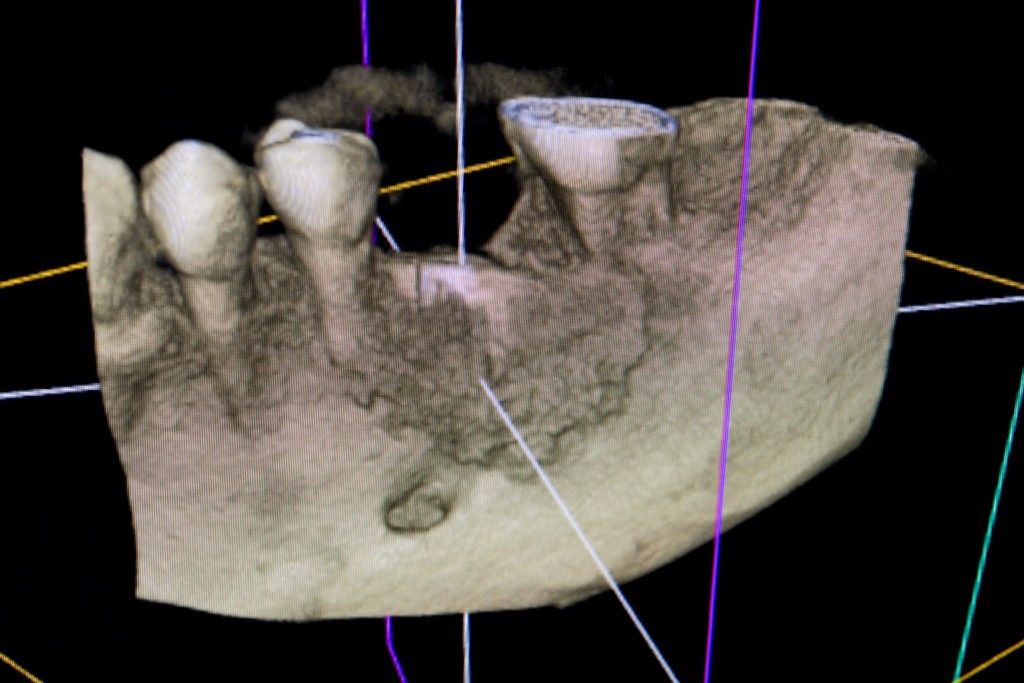

To kolejna metoda umożliwiająca precyzyjną odbudowę zadanego kształtu tkanki kostnej przy użyciu standardowych materiałów kościotwórczych, kości własnej lub PRF oraz zewnętrznego rusztowania w postaci siatki z biozgodnego stopu tytanu. Siatka jest indywidualnie projektowana w technologii CAD CAM i następnie drukowana dla konkretnego przypadku.

Dotychczas stosowane stabilizatory zewnętrzne w formie siatek tytanowych używane do regeneracji kostnej lub w zabiegach odtwórczych w chirurgii szczękowo-twarzowej uwzględniały materiały ręcznie doginane i formowane podczas zabiegu operacyjnego. Zastosowanie technologii CAD CAM dla potrzeb druku materiałów przeznaczonych do indywidualnej rekonstrukcji kostnej znacznie poprawiło precyzję i jakość uzyskiwanych efektów. Wdrożenie biozgodnych stopów tytanu do druku siatek zdecydowanie ograniczyło odsetek powikłań zapalnych.

Siatki stanowią stabilną obudowę – ograniczenie nadające kształt regenerowanej kości przy użyciu upakowanego pod nią materiału. Utrzymują i stabilizują rozdrobniony granulat kościotwórczy, co jest warunkiem prawidłowego procesu gojenia, jednocześnie nadając anatomiczny kształt i zakres odbudowie kostnej sprzed jej zaniku.

Precyzja projektu druku siatki bazuje na dokładności odwzorowania kształtu kości w stożkowej tomografii komputerowej CBCT, co zapewnia ich dobre przyleganie do podłoża kostnego oraz ogranicza powstawanie powikłań w postaci obnażania się siatek.

Ten rodzaj odbudowy kostnej stosowany jest w sytuacjach złożonych, trójwymiarowych 3D ubytków kości, przy których standardowe metody odbudowy są niewystarczające. Ilość kości, którą możemy uzyskać, stosując tę metodę, to nawet kilka centymetrów sześciennych.

Metoda rekonstrukcji kostnej w oparciu o indywidualnie drukowane siatki z tytanu dla implantacji wszczepów śródkostnych stosowana jest najczęściej jako dwuetapowa. W pierwszym etapie odbudowywana jest kość, natomiast implanty wszczepiane są po okresie 4–6 miesięcy. Na wgojenie implantów oczekujemy od 4 do 6 miesięcy w zależności od miejsca ich lokalizacji. Siatka tytanowa po spełnieniu swojej funkcji rusztowania dla odbudowującej się kości jest następnie usuwana w dniu wszczepienia implantu. Jeżeli kość spełnia odpowiednie warunki, istnieje możliwość zastosowania modyfikacji siatki tytanowej, która umożliwia jednoczesne wprowadzenie implantów wraz z odbudową kostną. Wariant ten skraca czas od pierwszego zabiegu do wykonania gotowych koron protetycznych na wprowadzonych implantach.